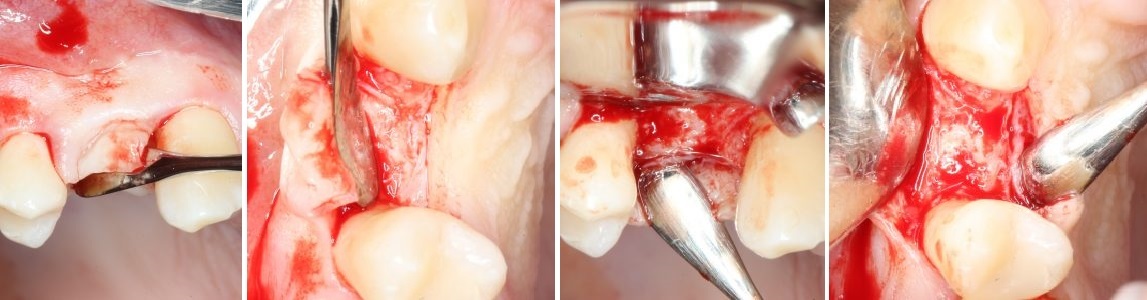

После проведенной анестезии, при помощи скальпеля производится - разрез, а так называемого распатора - скелетирование кости. (отделение надкостницы от компактного вещества кости).

Разрез:

Скелетирование кости: